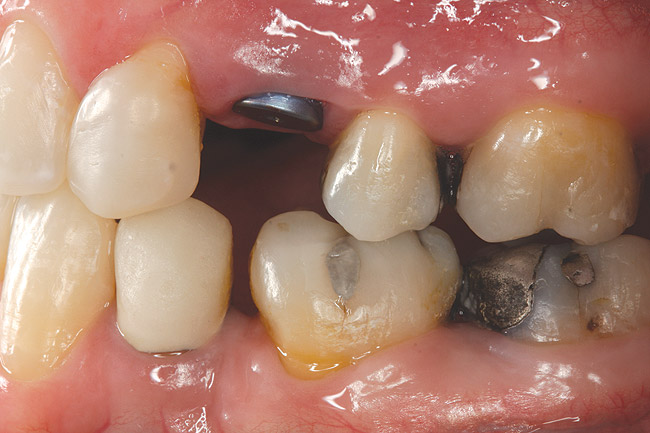

Fig 11. Corticotomy SFOT. A 42-year-old male presented with a history of extraction orthodontic therapy.

Figure 11

Fig 12 (and Fig 13). Incisors were too upright and had severe incisal wear. He was concerned about esthetics of the worn teeth and his insufficient lip support. Progress photo and panorex 9 months after corticotomies were performed on Nos. 6 through 11. Previous extraction sites were reopened orthodontically to improve function and fill lip support. Incisal edges were restored provisionally with composite resin. Note that despite the creation of adequate spaces to replace missing teeth, there is inadequate room for placement of dental implants because of severe tipping of all the anterior teeth. Osteotomy SFOT may have been a better choice because it would have allowed needed alveoloskeletal correction (without excessive tipping) instead of the primarily dentoalveolar correction common in corticotomy SFOT. Restorative dentist: Brad Jones, DDS.

Fig 13 (and Fig 12). Incisors were too upright and had severe incisal wear. He was concerned about esthetics of the worn teeth and his insufficient lip support. Progress photo and panorex 9 months after corticotomies were performed on Nos. 6 through 11.